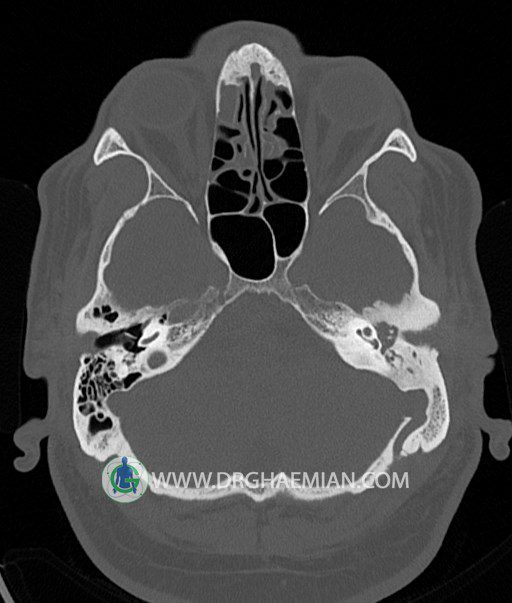

سی تی اسکن گوش داخلی به رادیولوژیست اجازه می دهد تا سطوح مختلف، یا اسلایس هایی از استخوان های که از جمجه به گوش می روند را از طریق امواج ایکس چرخشی مشاهده کند. در این کیس اودیت مدیا، ماستوئیدیت مزمن، اوتیت خارجی، انحراف سپتوم بینی، کونکا بولوزا و افزایش ضخامت سینوس ها مشاهده می شود.

در HRCT از استخوان تمپورال با مقاطع آگزيال ، ساژيتال و کرونال ظريف ( 0.6 mm ) :

– اپاسيتي و اسکلروزيس ماستوئيد چپ نشانه ماستوئيديت مزمن

– اپاسيتي کانال گوش خارجي ناشي از دانسيتي نسج نرمي مطرح کننده external otitis

– انحراف سپتوم مياني بيني به راست

– کونکا بولوزا در کونکاي مياني چپ و

– افزايش ضخامت مخاطي در سينوس هاي اتموئيد و ماگزيلاري